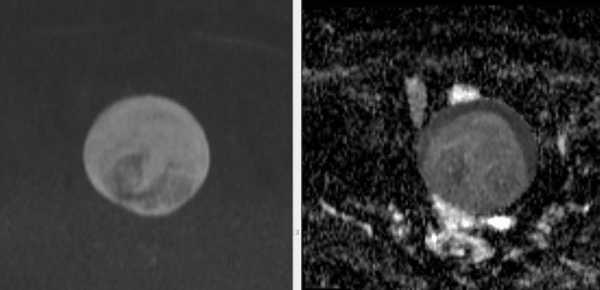

МРТ малого таза. Окружающая клетчатка с признаками отека, маточные трубы окружены неравномерно выраженным скоплением серозной жидкости.

Параовариально с обеих сторон определяются расширенные тубулярные структуры с неполными перегородками и утолщенными стенками, заполненные неоднородным вязким жидкостным содержимым, характеризующимся повышенным МР-сигналом на ДВИ с выраженным снижением ИКД (в,г) — расширенные маточные трубы с признаками белкового (гнойного) содержимого.